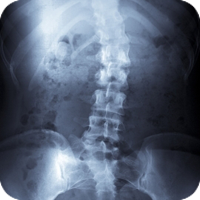

Scoliosis

Scoliosis is a sideways curve of the spine that causes stiffness and pain. People with scoliosis have a sideways curve in their spine that makes an "S" or "C" shape.

Scoliosis is derived from the Greek term meaning curvature. People with scoliosis have a sideways curve in their spine that makes an "S" or "C" shape. The vertebrae can rotate at the thoracic level of the spine causing this curve and resulting in a hump near the rib cage. If the curve is more than 60 degrees it is considered serious. Usually this curve makes the waist or shoulders uneven. And unlike the normal curvature of the spine, adjusting your posture will not correct the problem.